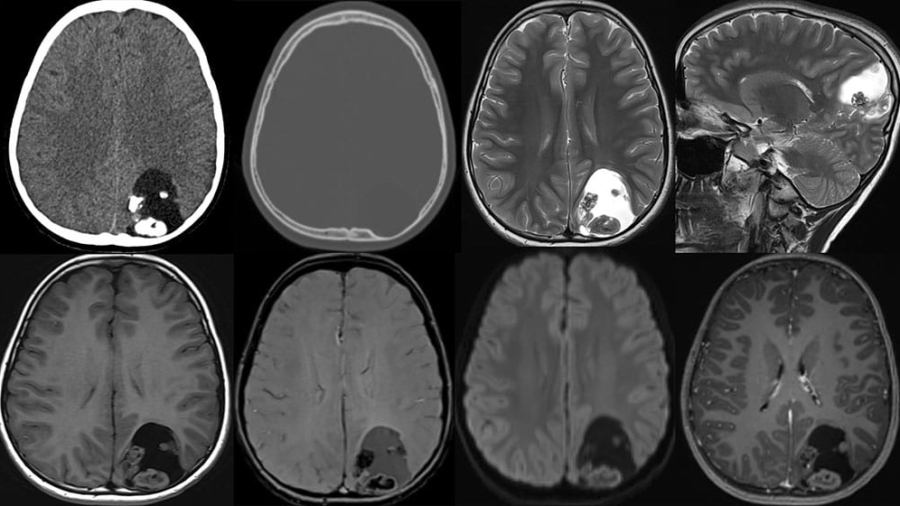

59-Year-old lady, a known case of chronic liver disease with portal hypertension presented with progressive left hemiparesis over three months.